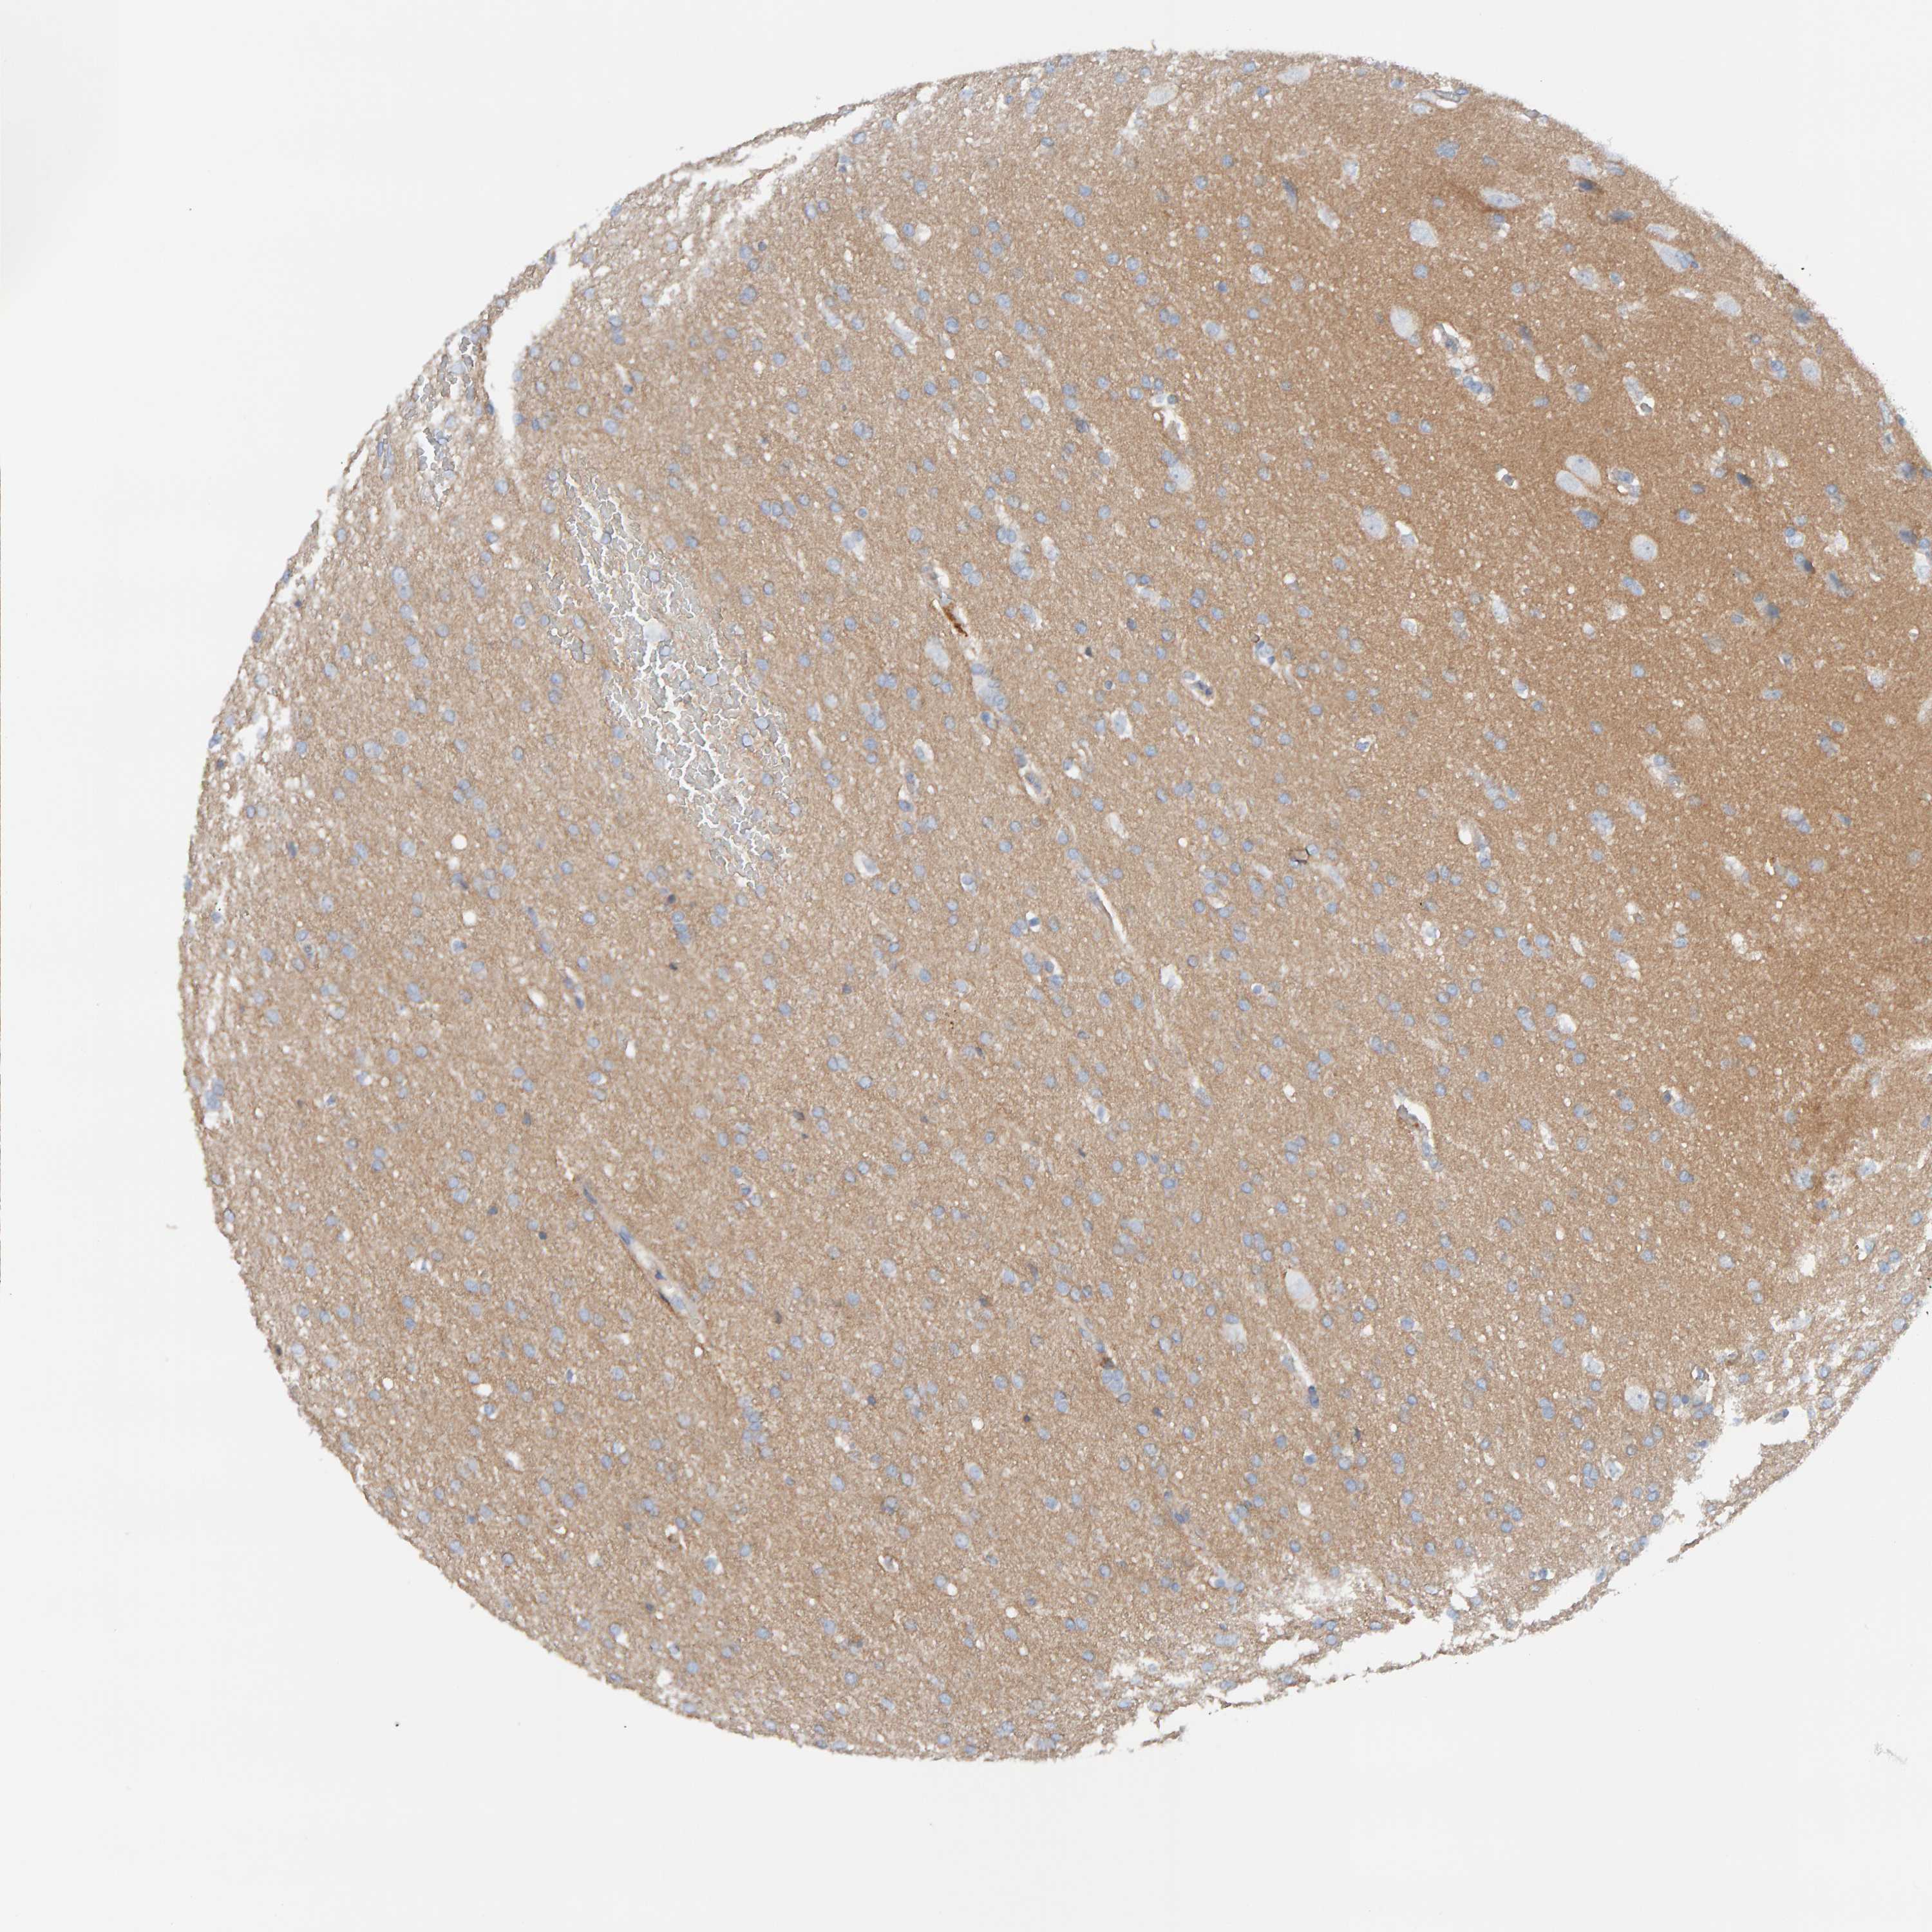

GLIOMA - Protein expressioni

A mouse-over function shows sample information and annotation data. Click on an image to view it in a full screen mode. Samples can be filtered based on level of antibody staining by selecting one or several of the following categories: high, medium, low and not detected. The assay and annotation is described here.

Note that samples used for immunohistochemistry by the Human Protein Atlas do not correspond to samples in the TCGA dataset.

Antibody stainingi

Antibody staining in the annotated cell types in the current human tissue is reported as not detected, low, medium, or high, based on conventional immunohistochemistry profiling in selected tissues. This score is based on the combination of the staining intensity and fraction of stained cells.

Each image is clickable and will lead to virtual microscopy that enables deeper exploration of all samples and also displays staining intensity scores, fraction scores and subcellular localization as well as patient and tissue information for each sample.

Antibody HPA023887

Antibody CAB005034

Antibody CAB018387

Staining

High

Medium

Low

Not detected

Intensity

Strong

Moderate

Weak

Negative

Quantity

>75%

75%-25%

<25%

None

Location

Nuclear

Cytoplasmic/membranous

Cytoplasmic/membranous,nuclear

Glioma, malignant, High grade

Glioma, malignant, Low grade

Glioma, malignant, NOS